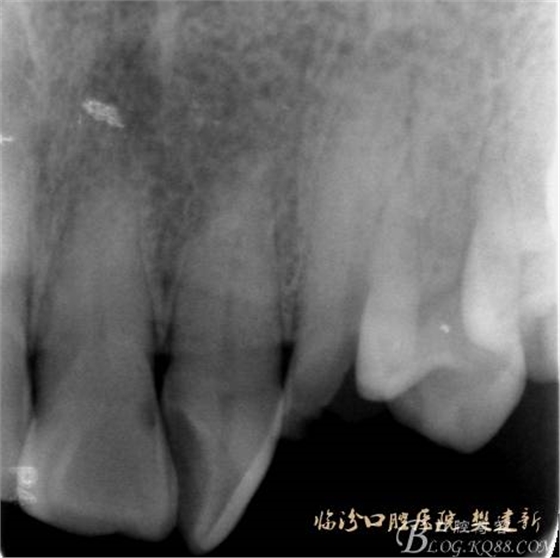

圖2 治療前X片: 23殘根,根尖區(qū)骨密度降低.